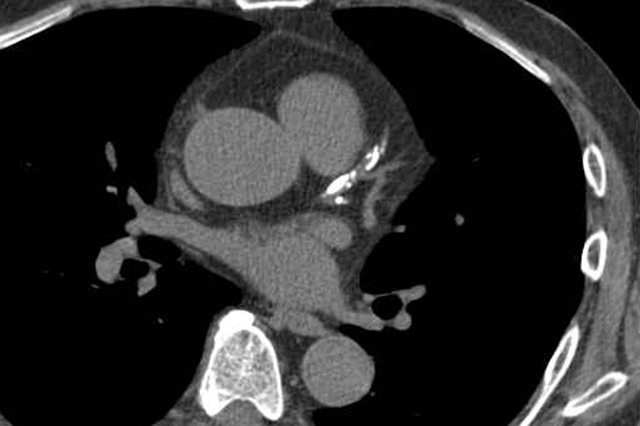

복부 CT는 X선을 이용해 인체를 단면 영상으로 촬영하는 검사로, 단순 CT와 조영제를 사용하는 조영 CT로 나뉩니다. 단순 CT는 결석, 출혈, 석회화 병변 확인에 유리하며, 조영 CT는 종양, 염증, 혈관 이상, 장기 손상 여부를 평가하는 데 적합합니다.

복부 CT는 주요 혈관 상태를 확인하는 데도 유용합니다. 조영 CT를 통해 혈류 상태를 평가할 수 있습니다.